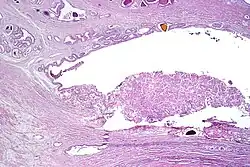

-

Intraductal carcinoma of the prostate with an infiltrative growth pattern may be morphologically difficult to distinguish from invasive cancer. One focus shows comedonecrosis (arrow), morphologically suggesting Gleason pattern 5 invasive carcinoma (a haematoxylin and eosin, b CK5/6)[20] -